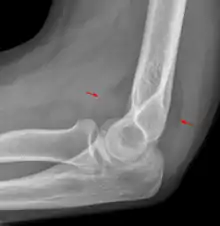

The fat pad sign, also known as the sail sign, is a potential finding on elbow radiography which suggests a fracture of one or more bones at the elbow. It is may indicate an occult fracture that is not directly visible. Its name derives from the fact that it has the shape of a spinnaker (sail).[1] It is caused by displacement of the fat pad around the elbow joint. Both anterior and posterior fat pad signs exist, and both can be found on the same X-ray.

In children, a posterior fat pad sign suggests a condylar fracture of the humerus. In adults it suggests a radial head fracture.

The fat pad sign is invaluable in assessing for the presence of an intra-articular fracture of the elbow. An anterior fat pad is often normal. However a posterior fat pad seen on a lateral x-ray of the elbow is always abnormal. The patient will be unable to flex their elbow and requires orthopaedic input.[2]

The posterior fat pad is normally pressed in the olecranon fossa by the triceps tendon, and hence invisible on lateral radiograph of the elbow.[3] When there is a fracture of the distal humerus, or other pathology involving the elbow joint, inflammation develops around the synovial membrane forcing the fat pad out of its normal physiologic resting place. This is visible as the "posterior fat pad sign" and is often the only visible marker of a fracture, particularly in the pediatrics population.